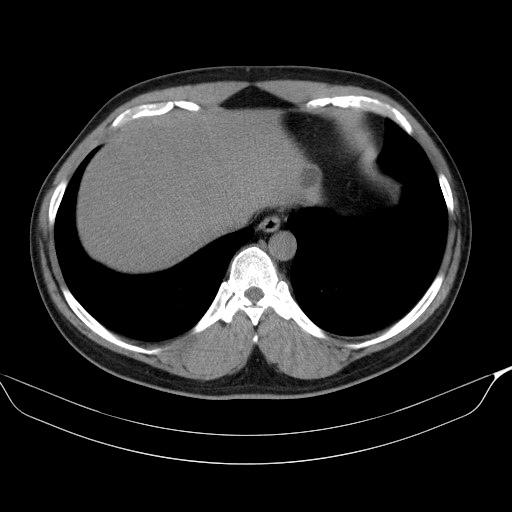

이 환자는 폐암의 선별검사를 위해 low-dose chest CT도 같이 시행하였는데, 초음파영상에서는 발견하지 못했던 저음영의 단순낭종을 간좌엽 윗부분에서 발견하였습니다.

이번 사례에서처럼 초음파영상 중에는 간좌엽을 별다른 지장 없이 다 확인했다고 믿고 넘어갔으나, 다른 검사에서 미처 발견하지 못했던 병변을 발견하는 경우가 종종 발생합니다. 특히 간 좌엽의 윗부분은 윗쪽 종격동의 fat tissue와 stomach gas shadow와 같이 초음파 빔의 진행을 방해하는 구조물들이 많기 때문에 간 우엽의 지붕부위 못지 않게 주의를 기울여야 하는 부위입니다.